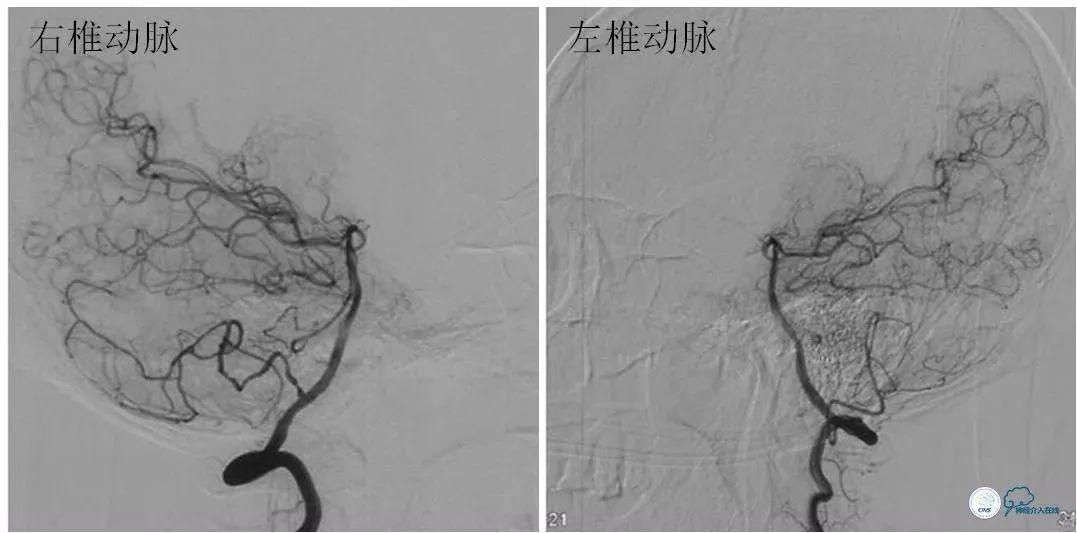

DSA:左颈内动脉C6-7段重度狭窄,狭窄程度重,病变较长,前向血流减慢(图4,5),后循环造影显示后循环向前循环侧支代偿不足(图6)。

图6